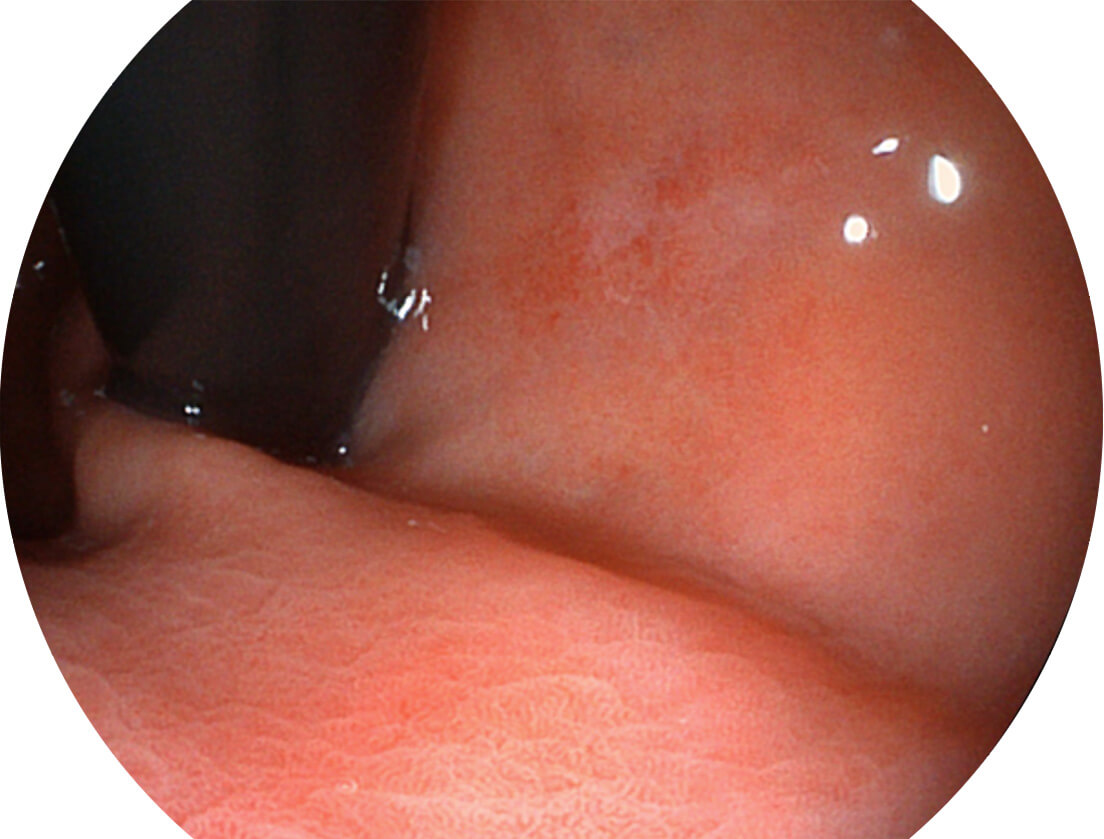

白光图像

强调浅层黏膜结构的同时,保证照明亮度和提升浅层微血管与中层血管颜色对比度,病变边界更清晰。